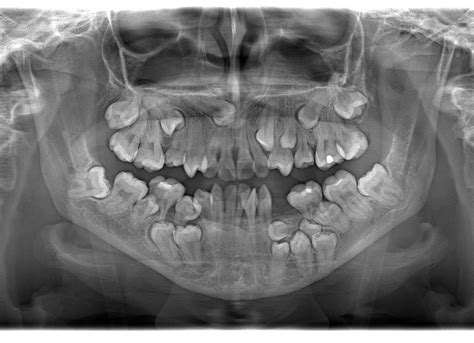

Radiografía panorámica utilizada para el diagnóstico de hiperdoncia.

El diagnóstico de la hiperdoncia generalmente comienza con una exploración clínica exhaustiva realizada por uno de nuestros dentistas. Durante este examen, se realiza un examen de la boca del paciente en busca de signos visibles de dientes adicionales. Por esto, se recurre a radiografías dentales para obtener una visión más detallada de la dentición del paciente. Las radiografías permiten observar no sólo los dientes visibles, sino también aquellos dientes que están por debajo de la superficie, como los dientes impactados o los que aún no han erupcionado.

Aunque la hiperdoncia puede ser detectada a través de una exploración clínica básica y radiografías, es esencial que el diagnóstico y tratamiento sean gestionados por un dentista especializado. Un dentista especializado en ortodoncia o cirugía maxilofacial será capaz de evaluar adecuadamente la situación y determinar el tratamiento más adecuado para cada caso.